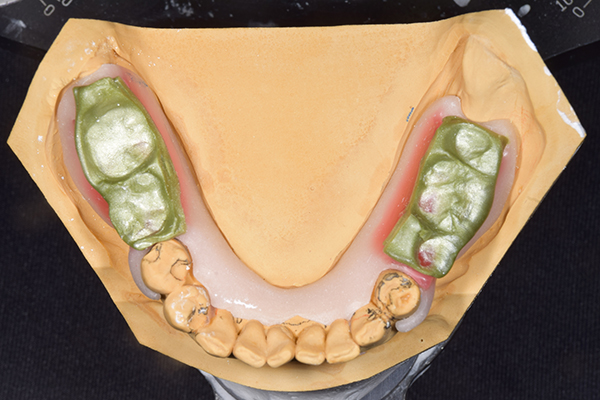

ケース1(自費の部分入れ歯)

前歯が折れて当院にいらっしゃいました。 過去に下の入れ歯を作ったが、合わなくなってずっと入れ歯をいれていらっしゃらない患者様でした。 これは奥歯で噛むことができないため、前歯で噛むことを繰り返したために、負担に耐えられなくなった前歯が折れてかぶせ物ごと 外れてしまったのだと考えられます。 痛くない、違和感の少ない、下の入れ歯を作ることがこの方のゴールであると考えられました。

シリコンで精密な型取りを行いました。

噛み合わせチェックです。 奥歯でしっかりものが噛める様に高さを決めていきました。